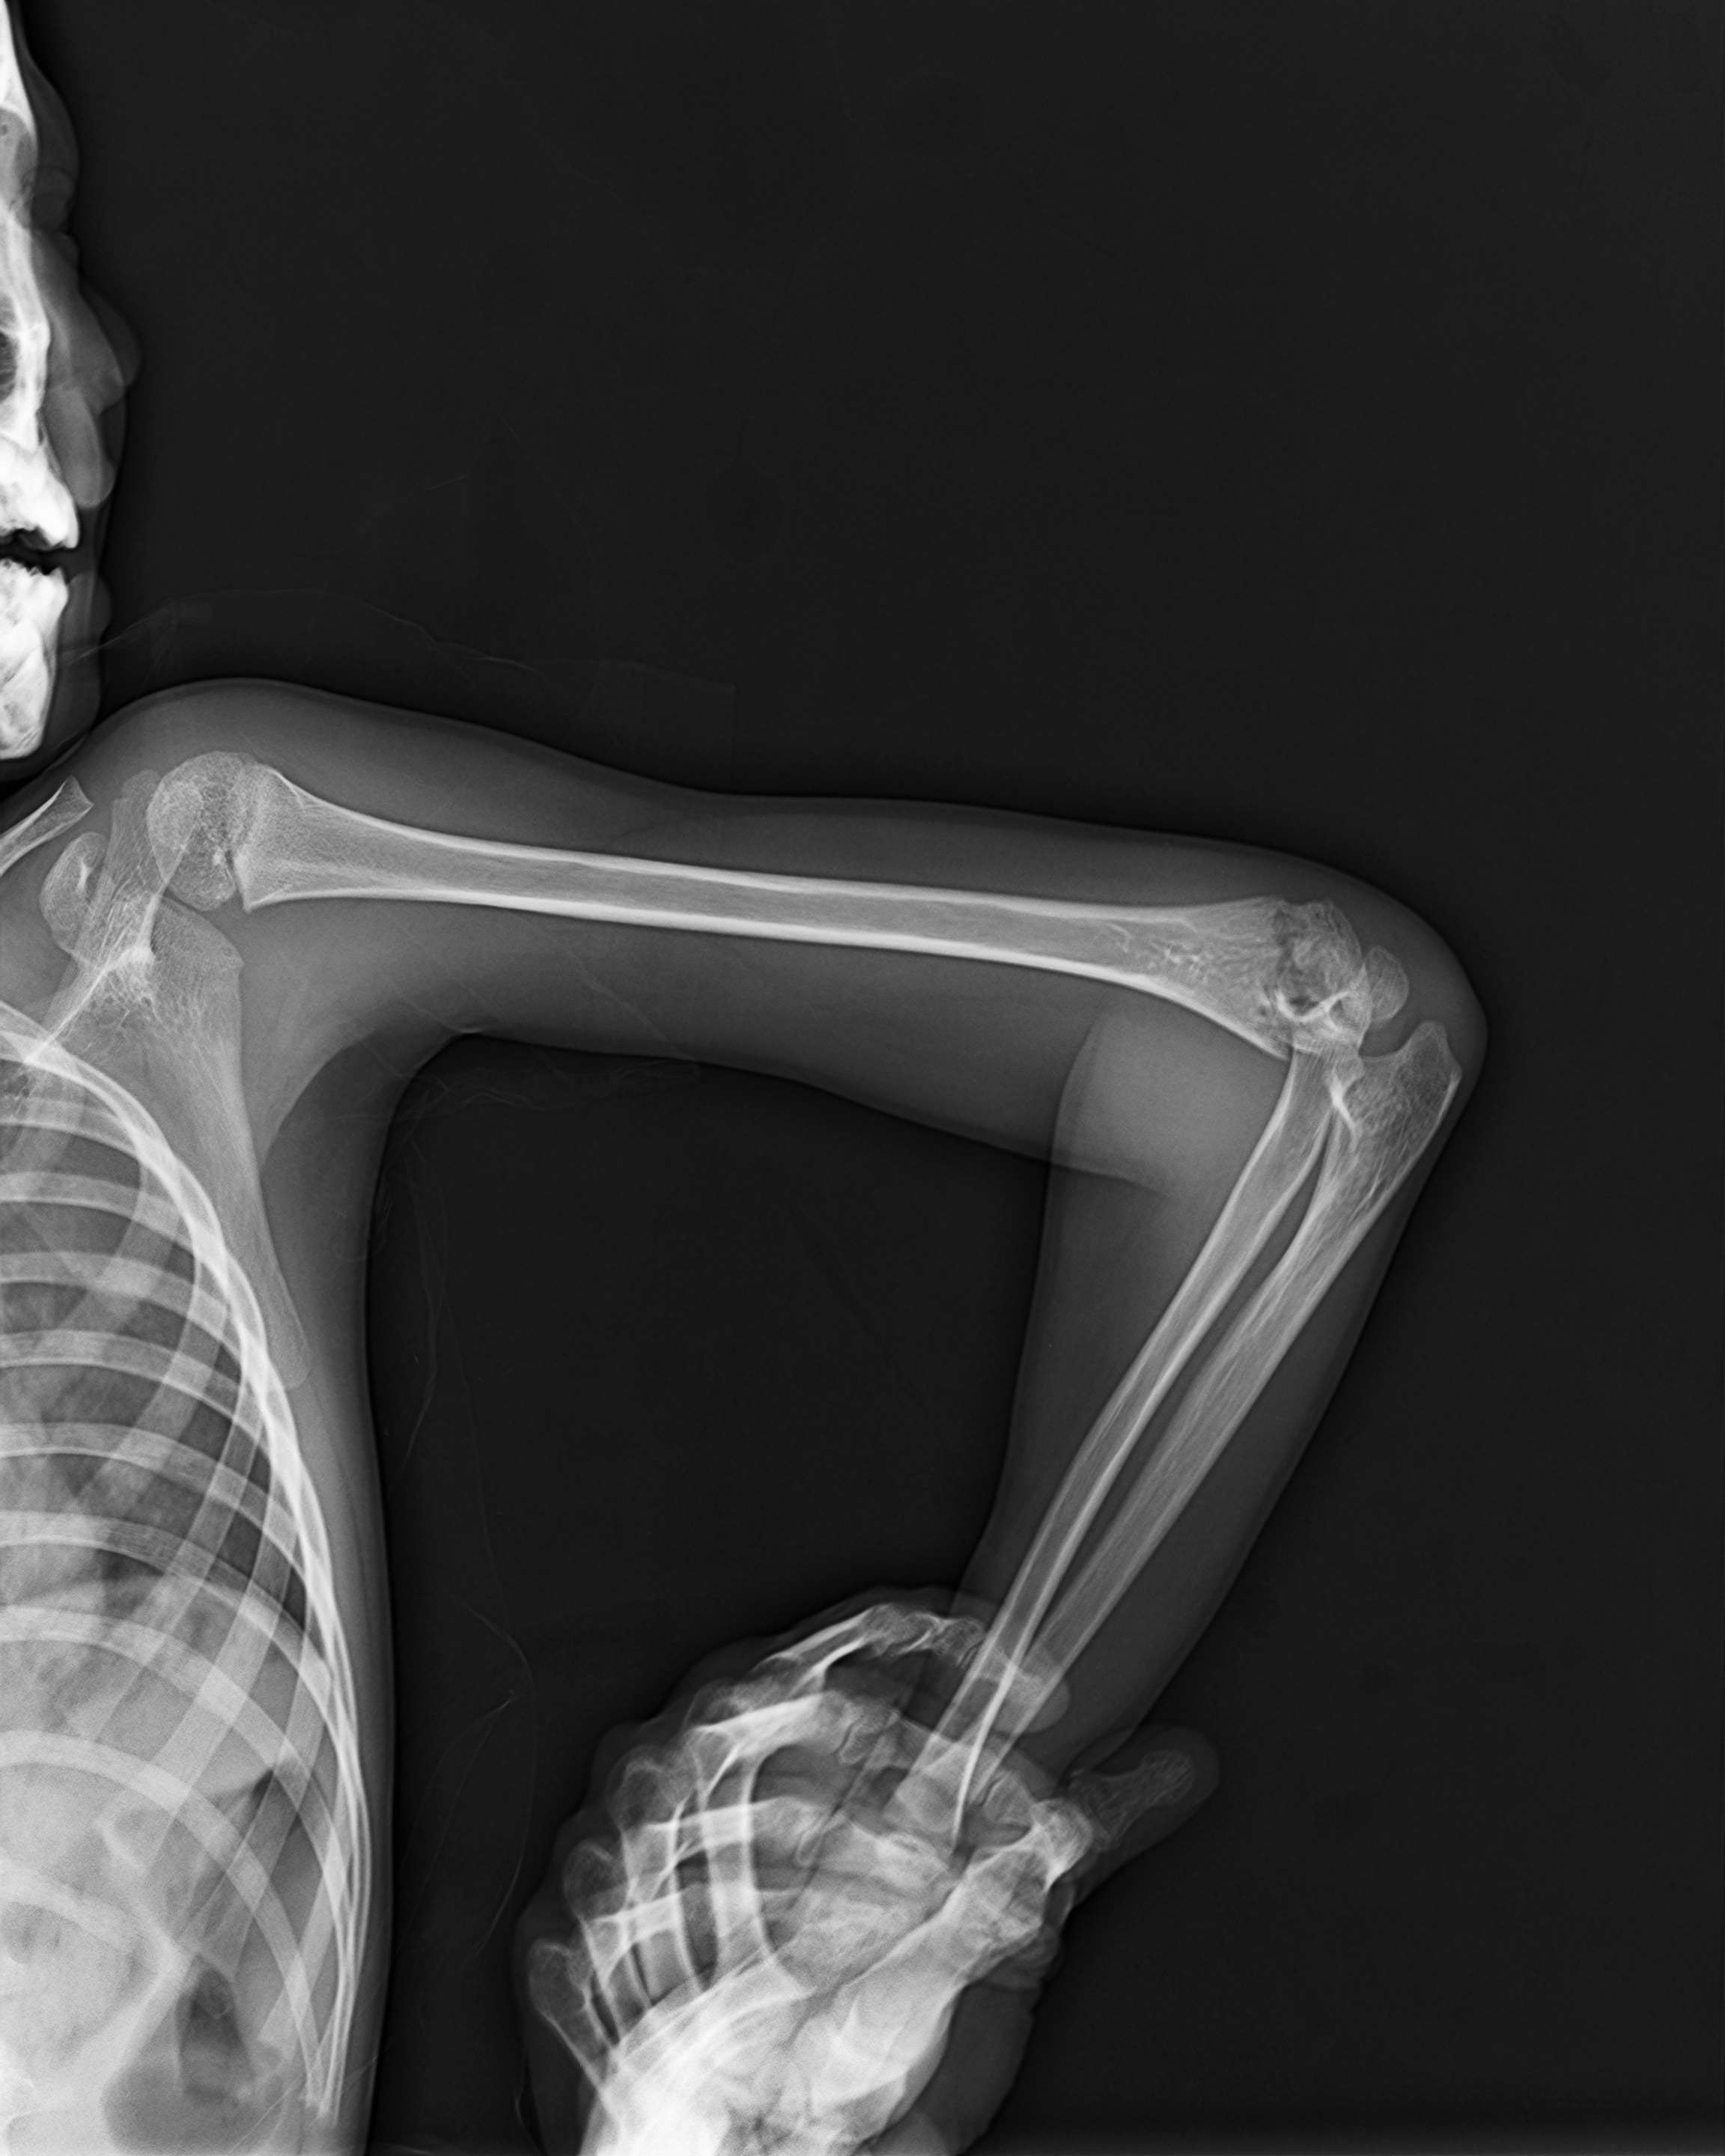

AI-Powered Fracture Detection & Classification

Upload X-ray images via drag-and-drop or select sample images for AI-powered fracture analysis.

Get instant AI diagnosis with confidence scores and medical recommendations in 5-10 seconds.

Review detailed findings and recommendations in the interactive canvas sidebar.

Advanced AI medical imaging tool developed at West Visayas State University for orthopedic fracture detection and classification.

Research-focused X-ray analysis system designed to assist medical professionals in diagnostic imaging.